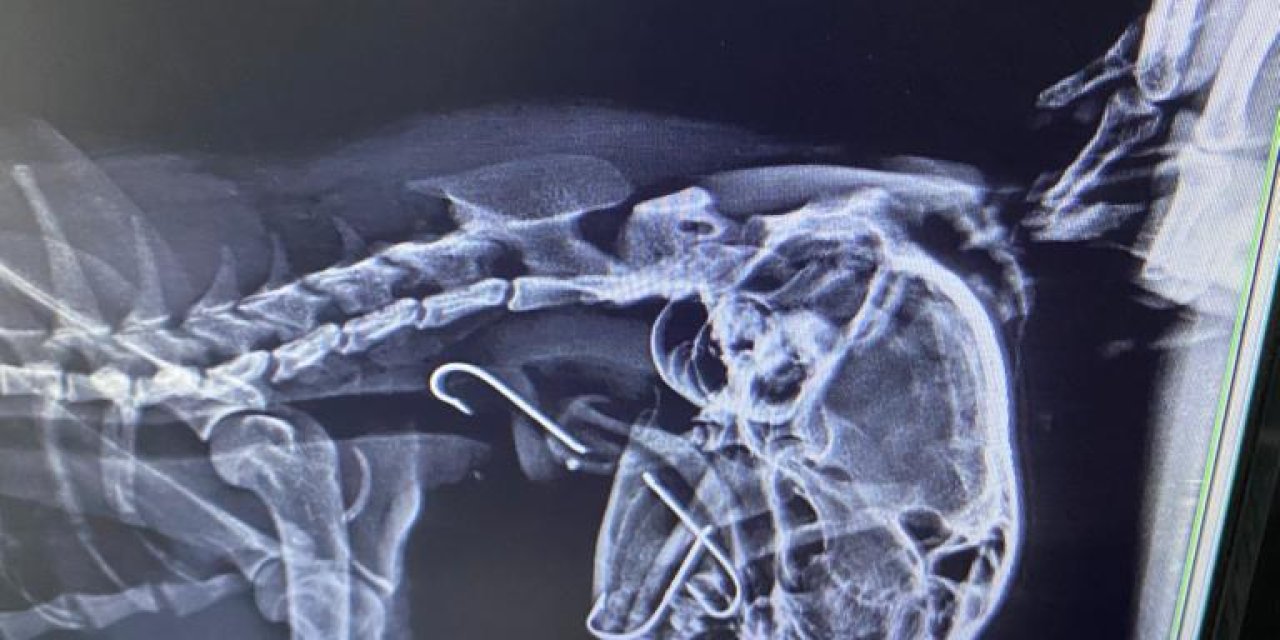

Boğazına 3 Olta Kancası Takılan Kedi, Tedavi Edildi